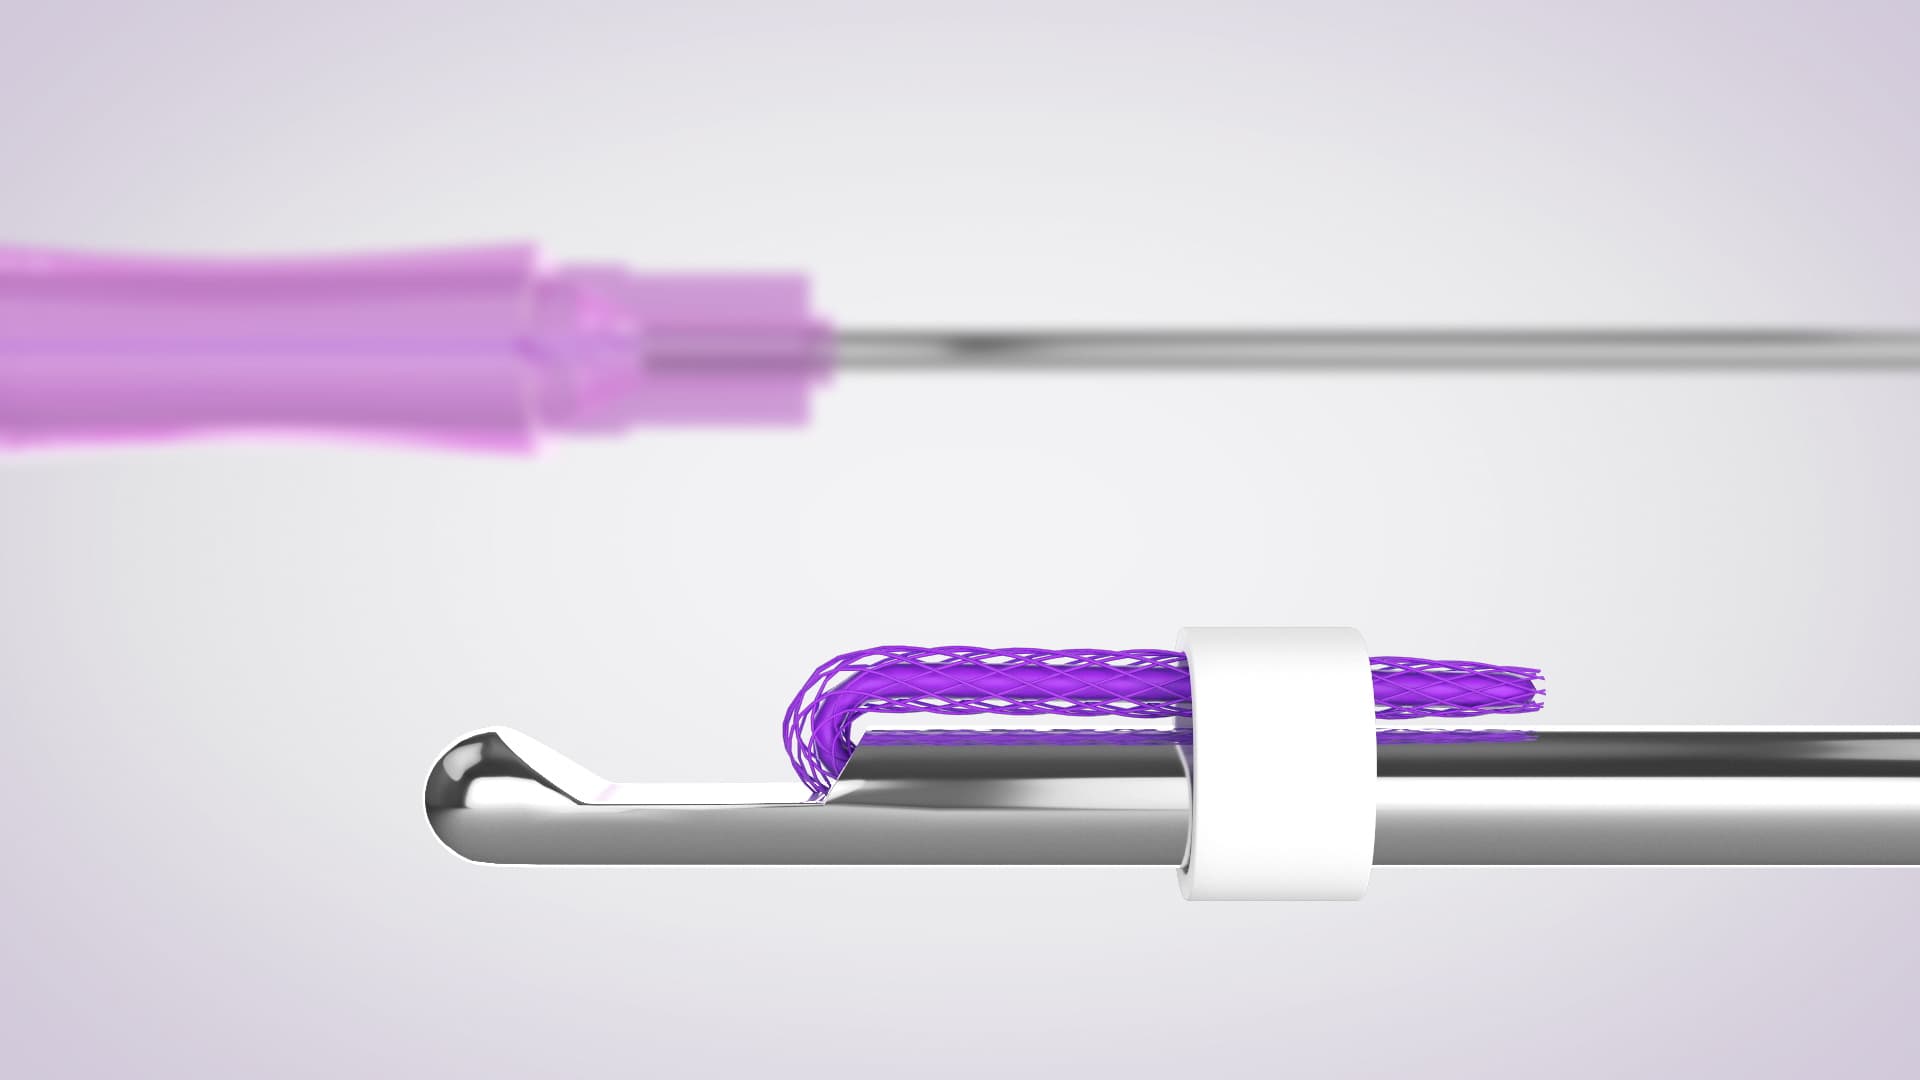

Technology, Principle, Core

Core Technology

Core technology and principles